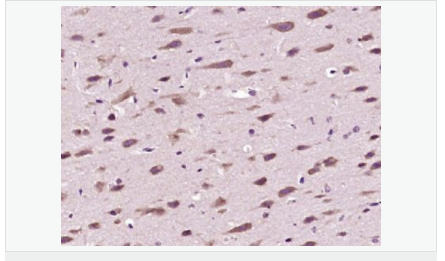

image.png